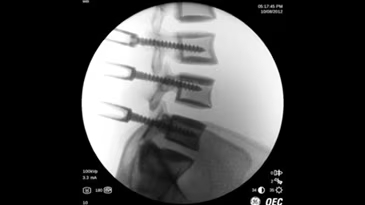

Brivo OEC 785 - это надёжная С-дуга, которая работает вместе с вами, эффективно устраняя сложности визуализации и позволяя хирургу сфокусироваться на пациенте. Отличительной чертой системы Brivo OEC 785 является высокое качество визуализации, на которое можно рассчитывать изо дня в день. Вы можете доверить технологиям GE Healthcare точное и эффективное получение чётких изображений, даже при низкой дозе. Автоматизированные смарт-функции Brivo OEC созданы, чтобы вы получали изображения высокого качества, даже в клинически сложных случаях. Подобно тому, как орлиный глаз может различить движение и малозаметные объекты, эта система делает упор на получение изображения высокой точности при любой степени клинической сложности.

- Четкая визуализация и клиническая надежность

Получение четких изображений с помощью «умной» цепи визуализации. - Удобная работа